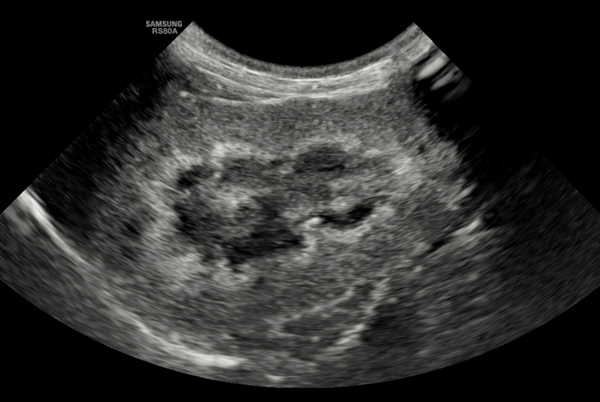

Figure 2. Longitudinal section of the right kidney of a 15-year-old MN domestic short haired cat showing a medullary rim sign (band-like) with mild loss of corticomedullary definition. These findings are suggestive of CKD, but insufficient to confirm the diagnosis without other supportive findings.